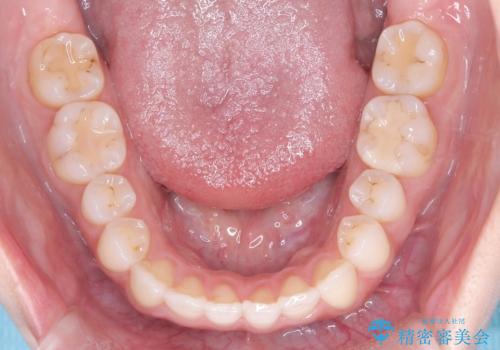

- 前歯の凸凹を主訴に来院された患者様です

骨格性の下顎前突傾向もあったため、臼歯関係の遠心移動も行うことで綺麗な仕上がりで矯正を終了することができました。

遠心移動を行うことで期間はかかりましたが、良い状態で仕上がっています。